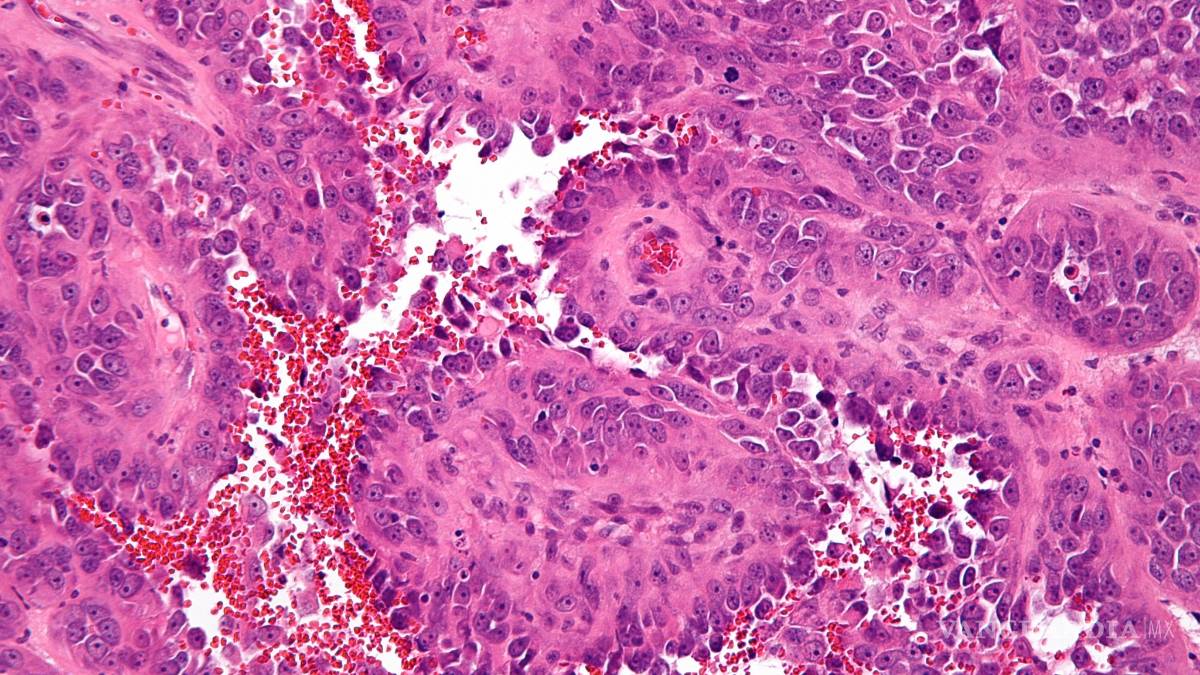

El estudio que es el resultado del Proyecto Angiosarcoma identificó nuevas causas del angiosarcoma, un cáncer poco frecuente de las paredes de los vasos sanguíneos, que podría aportar nuevas terapias.

Una investigación con pacientes del Broad Institute of MIT and Harvard (Estados Unidos) identificó nuevas causas del angiosarcoma, un cáncer poco frecuente de las paredes de los vasos sanguíneos, que podría aportar nuevas terapias, reveló hoy un artículo publicado en Nature Medicine.

Este tipo de cáncer, cuya agresividad es muy alta, puede ocurrir en cualquier parte del cuerpo, pero con mayor frecuencia se produce en la piel, el pecho, el hígado y el bazo.